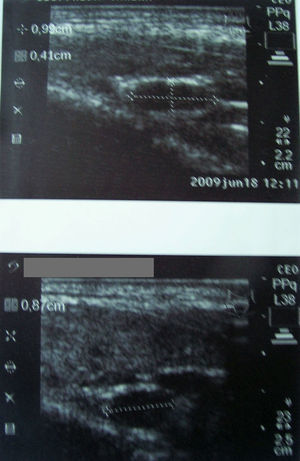

Se observó una imagen hipoecogénica ovoidea en topografía compatible con una glándula paratiroidea en 10 casos, y 2 o más (bilaterales) en 14 casos (figs. 1-2). El tamaño fue menor de 1cm en 10 pacientes, entre 1 y 1,5cm en 11, y mayores de 1,5cm en 3 casos (1,6; 1,7 y 1,8). Tenían ecografías previas en otros centros informadas como normales 9 pacientes. En la evolución se repitió la ecografía en 13 de nuestras pacientes, hallando imágenes similares a la primera en todas. La calcemia y la PTH fueron normales en 23 pacientes, con seguimiento en casi todas. La 25-hidroxivitaminaD se midió en la mitad de los casos, siendo mayor de 30ng/ml en un tercio, entre 20 y 30ng/ml en un tercio, y menor de 20ng/ml en otro tercio. No hubo relación entre tamaño o número de imágenes posiblemente paratiroideas y nivel de vitaminaD. Una de ellas, de 46 años, con una imagen de 6mm, tuvo PTH levemente elevada con calcemia normal, con vitaminaD en rango deseable (38ng/ml). En el seguimiento se elevó la calcemia, y un centellograma con MIBI fue positivo, por lo que fue intervenida quirúrgicamente con resultado de un adenoma paratiroideo.